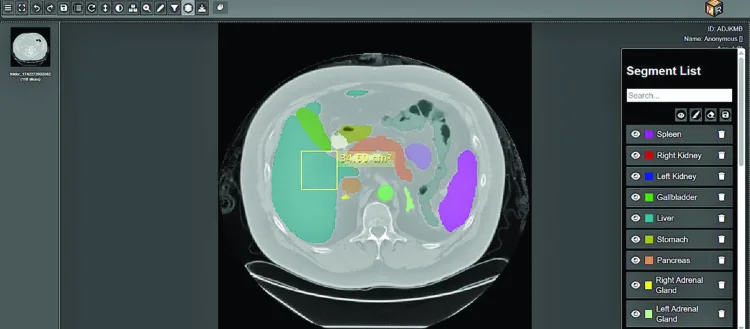

Easiofy’s ImagiXAI is an advanced AI-powered platform that transforms how Doctors analyse scans and plan treatments.

Trained on over 5 million medical images, it interprets CT, MRI, and PET scans, identifies tumors and organs at risk (OARs), and creates 3D visualisations using AR.

These models support radiation therapy, dosage planning, and surgical preparation- reducing work that once took weeks to just a single day.

Manual 90-minute tasks now take 15 minutes, leading to faster, safer treatments and improved patient outcomes.

Easiofy’s ImagiXAI functions as a Clinical Decision Support System (CDSS) that empowers doctors throughout the diagnosis and treatment process.

The system’s “human-in-the-loop AI” approach ensures that AI works with doctors, not instead of them, combining the precision of algorithms with human judgment.